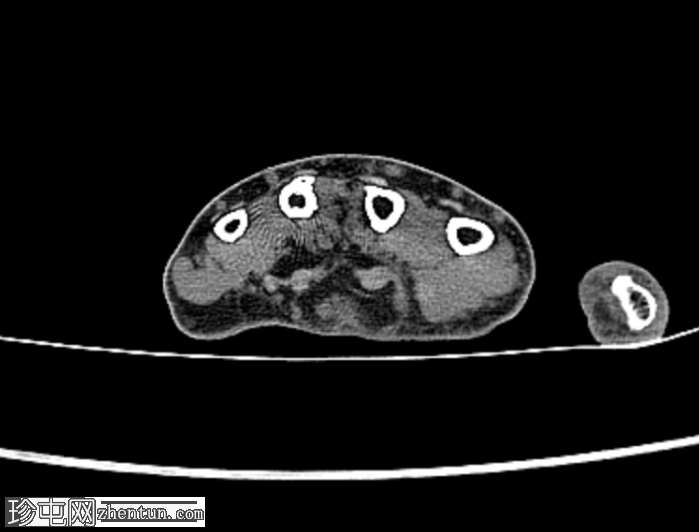

无名指和中指明显增大。患者掌骨和指骨骨质增生肥大,并伴有周围皮下脂肪过度增生。

CT 扫描显示骨质过度生长和肥大、皮下脂肪过度生长以及神经纤维脂肪瘤性错构瘤。